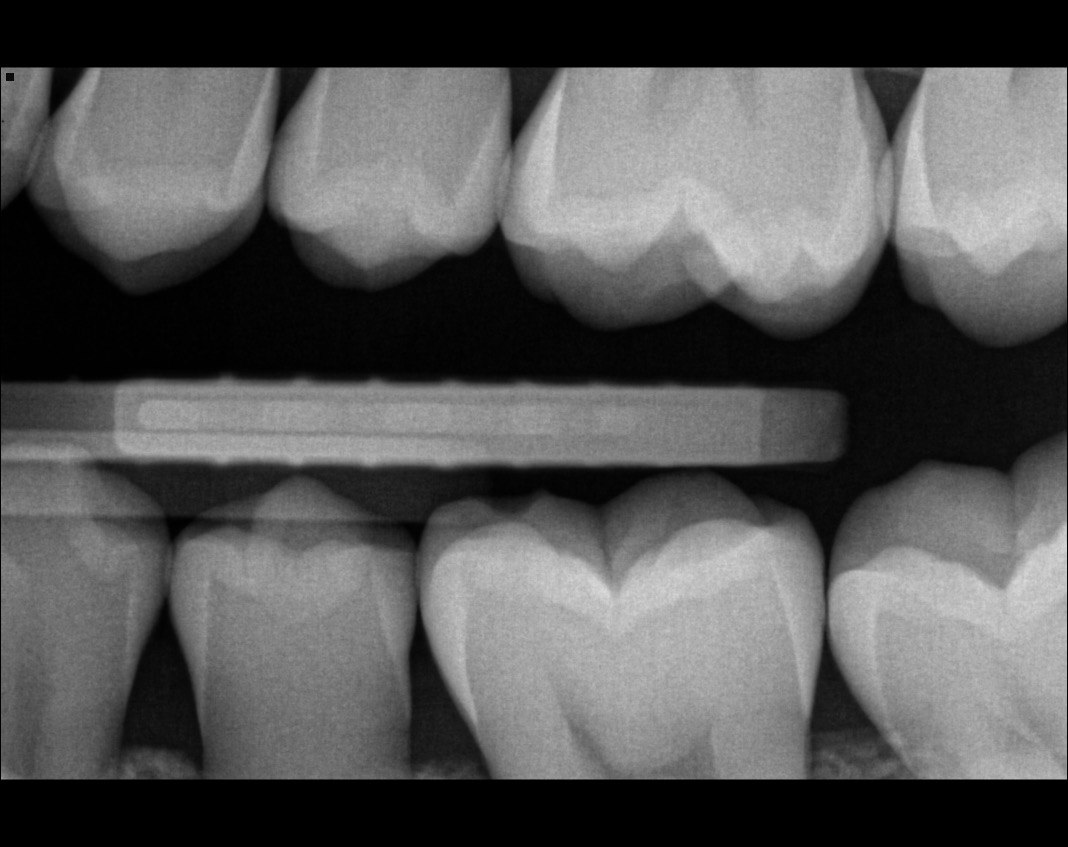

Question 4: what is the condition of the distal of the tooth # 4.1 and mesial of the tooth #3.1 respectively?

Question 5: Which surface shows recurrent caries?

Question 6: Which surface shows recurrent caries?